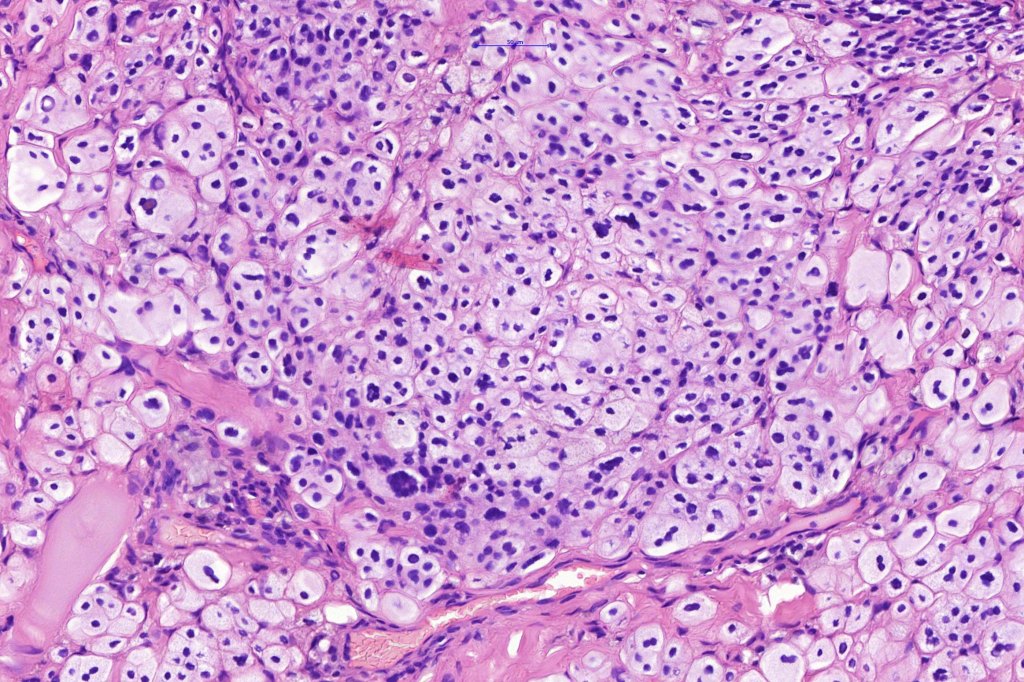

.Balloon cell change is most often seen in banal melanocytic nevi but it has also rarely been described in cellular blue nevus, dysplastic nevus, combined nevus, halo nevus & Spitz nevus. Lesions with <50% of balloon cells are sometimes described as nevi with balloon cells. Nevi with >50% balloon cells are described as balloon cell nevus.

.Balloon cell nevs genrally has uniform, hyperchromatic nuceli (as opposed to the vesicular nuclei with prominent nucleoli) seen in melanoma. Mitoses are absent.(In my experience, balloon cell melanoma is more common than balloon cell nevus).

. In some balloon cell nevi, the microvesicles may result in nuclear scalloping reminiscent of a sebaceous tumor. In cases where there is real doubt, immunohistochemistry (S100), SOX10) will resolve the problem.

The importance of the entity is that it must always be distinguished from balloon cell melanoma. All cases should be scrutinized very carefully for pleomorphism and mitotic activiy before rendering a diagnosis of balloon cell nevus.